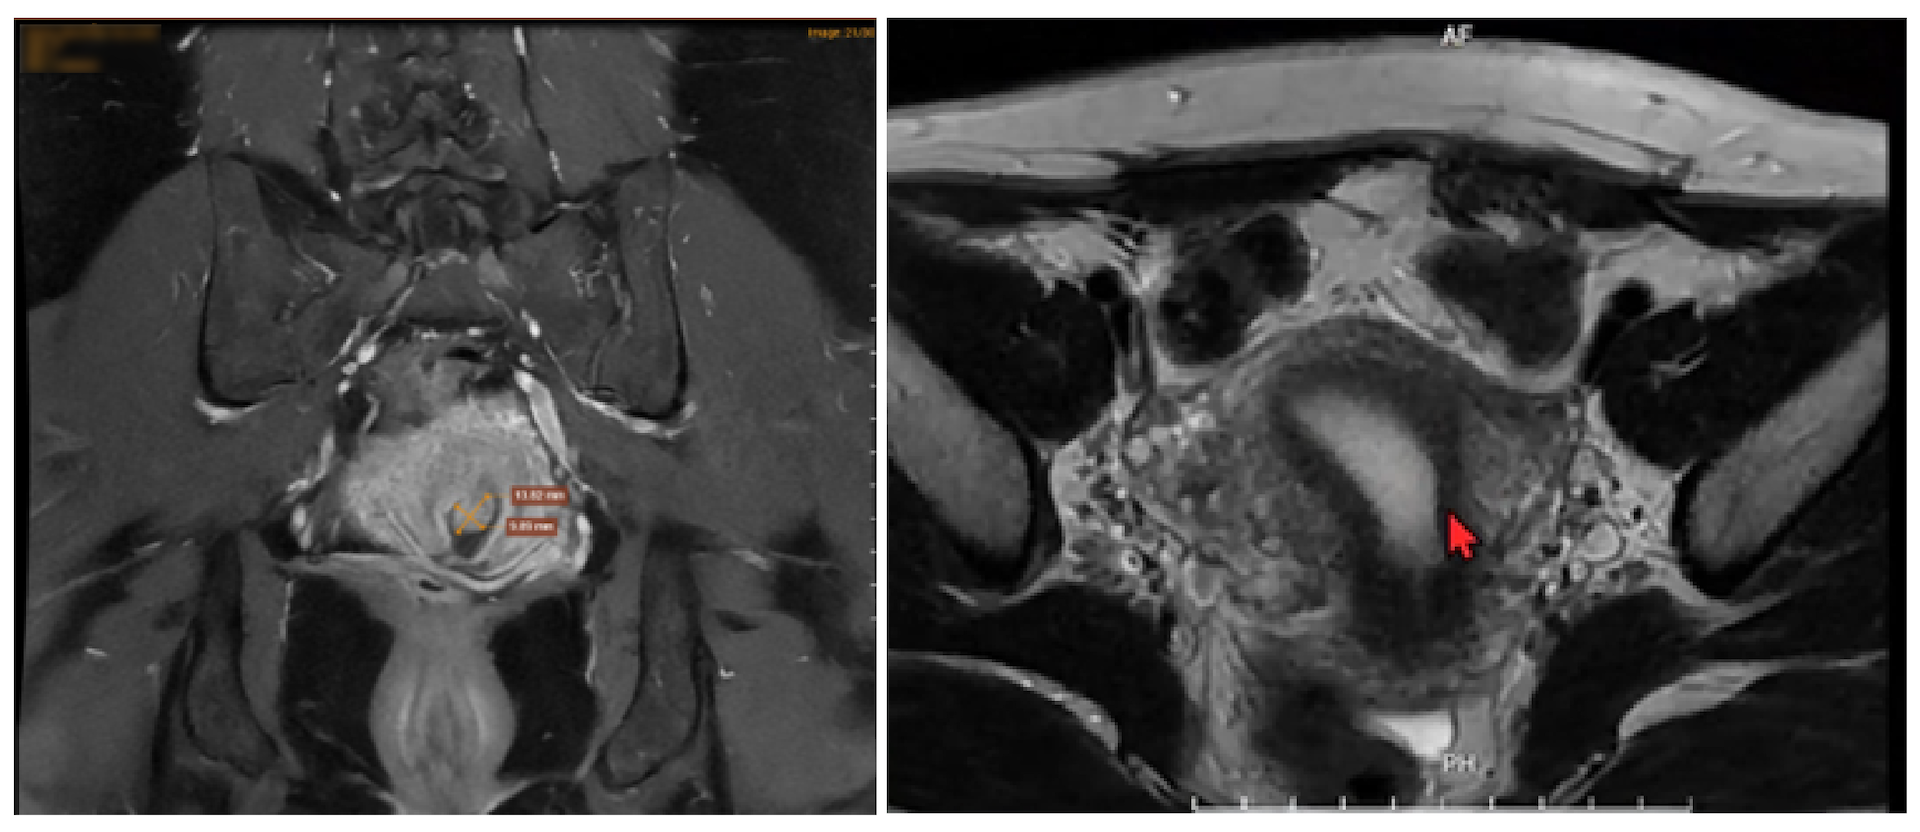

BS. Tính đã cùng chuyên gia Sản khoa MEDLATEC - PGS.TS Đặng Thị Minh Nguyệt - Phó Chủ nhiệm Bộ môn Phụ sản - Trường Đại học Y Hà Nội; Phó Trưởng Khoa Phụ nội tiết - Bệnh viện Sản Trung ương hội chẩn, chỉ định bệnh nhân thực hiện các cận lâm sàng cần thiết, đặc biệt là kỹ thuật chuyên sâu chụp MRI vùng chậu.

Kết quả đọc phim chụp MRI từ chuyên gia tại Trung tâm Chẩn đoán Hình ảnh MEDLATEC cho biết, nguyên nhân gây ra cơn đau mạn tính của bệnh nhân là do khối lạc nội mạc tử cung thành bụng, đồng thời cần theo dõi polyp ống cổ tử cung, nhân xơ vú phải và viêm tuyến giáp Hashimoto.